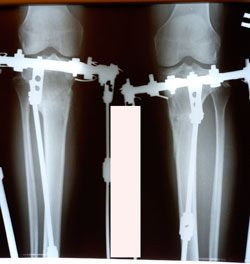

Исходник 33 года.

Дата операции - 09.10.2020

на фиксации

перед снятием аппаратов

Дата снятия аппаратов - 19.01.2021